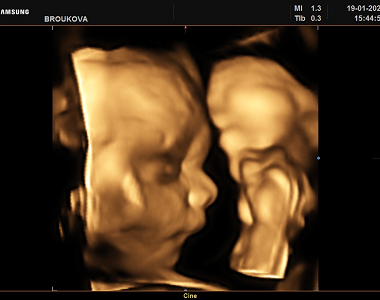

Mám za sebou první ultrazvuk, na kterém jsem viděla hlavičku, ruce i srdce, jen fotku zatím nemám. Je to zvláštní a kouzelný pocit, když se z lásky dvou lidí stvoří nový život. Při prvním těhotenství jsem se mnohem více bála, nejvíc asi porodu a té bolesti, ale nakonec jsem to zvládla i bez epidurálu. A nyní už vím, co mne čeká, a tak si ten pocit mnohem více užívám. Podle krevních testů je vše v pořádku, jen mi zjistili nižší hladiny železa, takže jsem dostala vitamíny. Šestnáctého prosince jsem objednaná myslím na screening a mám přijít na lačno v 7 ráno.